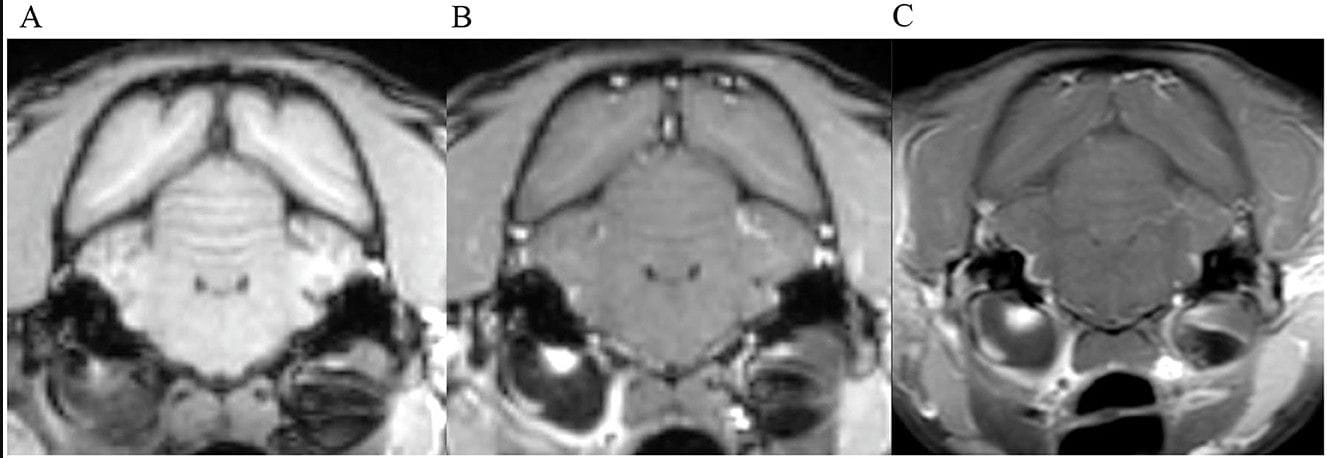

Transverse images at the level of the tympanic bullae. Example of perfect inter-observer agreement in the FS-TSE-T1W sequence in a cat. (A) is the T1W-pre-contrast image. 5/5 observers did not detect meningeal enhancement in the 3D-GRE-T1W (B), but agreed on detection in the FS-TSE-T1W (C). Meningeal enhancement was graded as focal and mild by all observers.